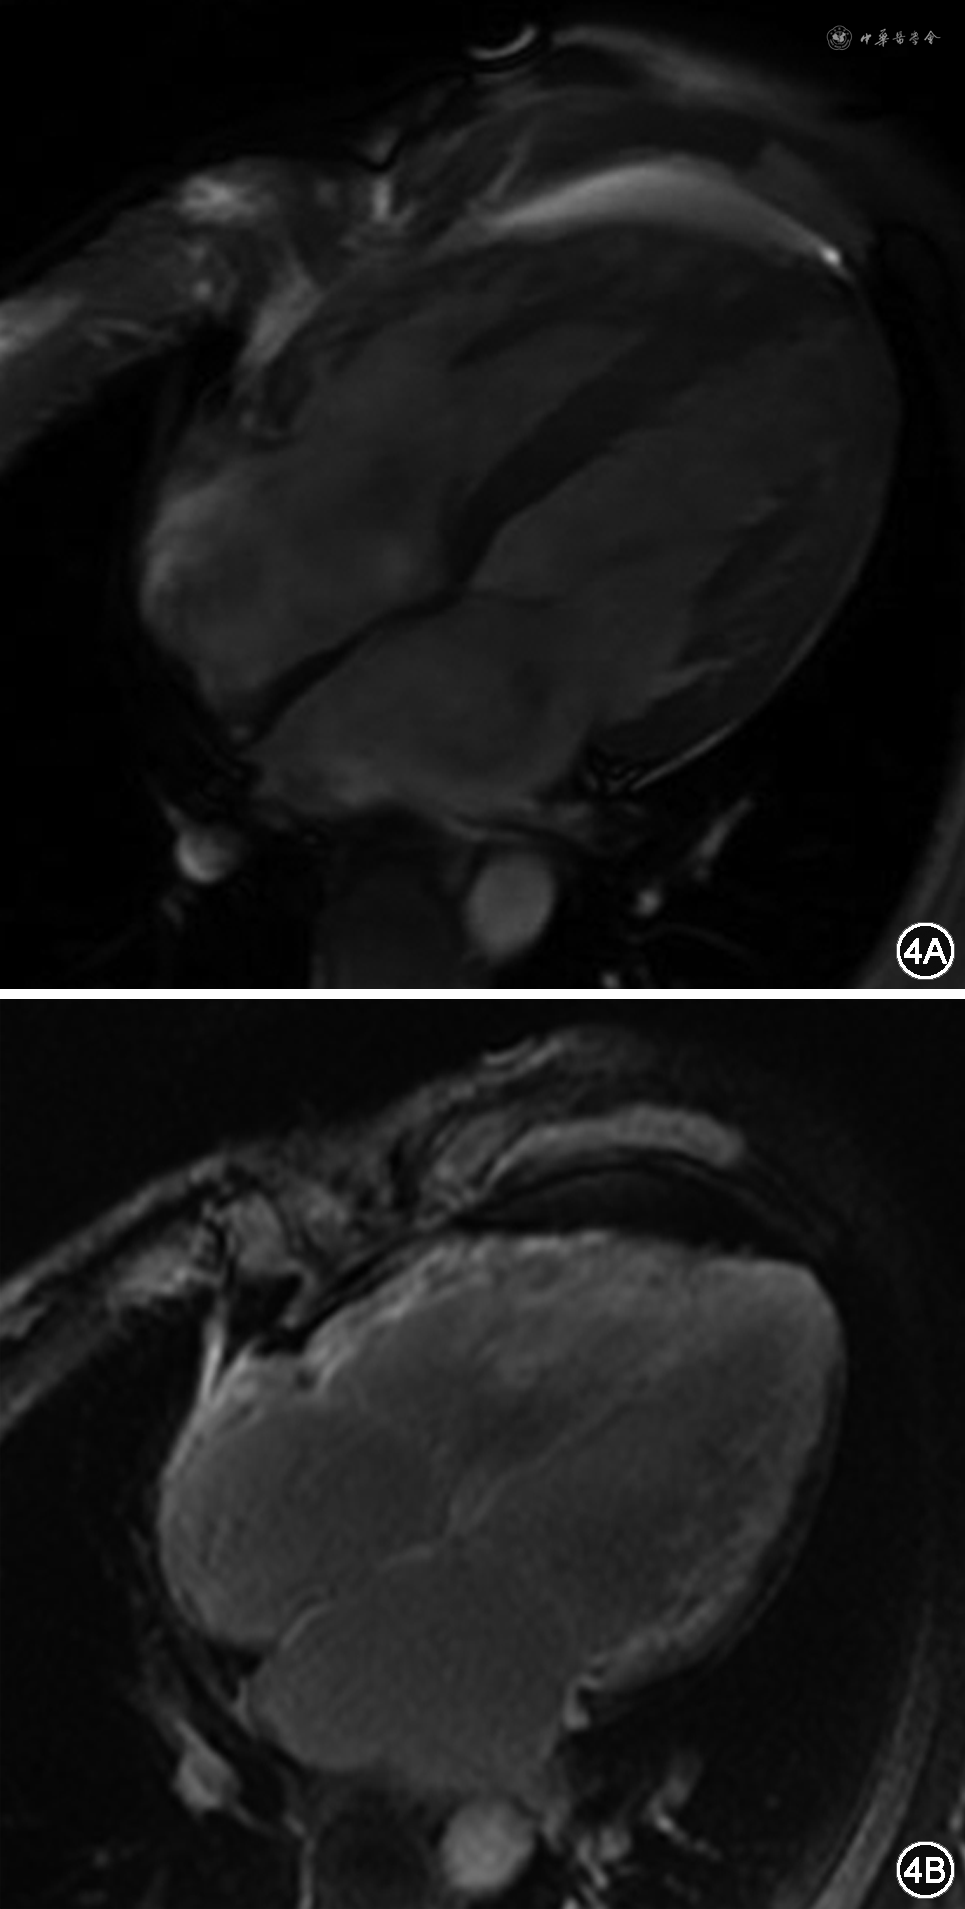

患者男性,41岁,主因“劳力性气短1月,加重1周”于2019年7月17日入院。2019年6月初活动后出现气短,不伴胸闷、胸痛、咽喉部紧缩感及肩背部放射痛,稍事休息可缓解,未诊治。7月10日起气短加重,劳动耐量较前下降,稍活动即感气短,平卧位时亦有气短发作,坐起后可缓解,不伴尿量减少、腹胀及双下肢水肿,为明确诊治来诊。既往史:否认高血压、糖尿病史。2019年4月15日因发热、咳嗽,最高体温为38.4 ℃,于外院行胸部CT示右肺中叶及左肺下叶炎性病灶,部分纤维化,少量心包积液,予抗感染、止咳等治疗后发热、咳嗽缓解。5月10日因左侧头疼伴左半身麻木、呃逆、呕吐行头颅磁共振成像(magnetic resonance imaging,MRI)检查提示急性脑梗死,经改善脑循环、脑保护、稳斑等治疗,无明显后遗症。个人史:吸烟史20年,平均20支/日。入院查体:神志清楚,半卧位,血压100/60 mmHg(1 mmHg=0.133 kPa),颈静脉无怒张,双肺呼吸音清,未闻及干、湿性啰音。心率105次/分,律齐,P2>A2,各瓣膜听诊区未闻及病理性杂音,移动性浊音阴性,双下肢无水肿。心电图:心率96次/分,V1-V4导联R波递增不良(图1)。胸片:双肺纹理增重,心界扩大(图2)。血常规、肝肾功能、电解质、凝血正常范围。心肌肌钙蛋白I(cardiac troponin I,cTnI)0.06 ng/mL,N末端B型利钠肽前体(N terminal-pro B type natriuretic peptide,NT-proBNP)6645.9 pg/mL。动脉血气分析:酸碱度(pH)7.409,二氧化碳分压(PCO2)33.5 mmHg,氧分压(PO2)70.4 mmHg。冠状动脉造影示:未见斑块及有意义狭窄。超声心动图示(图3):双心房增大,左心室、右心室稍大,左心室壁稍增厚,右心室壁厚约3.5 mm。二尖瓣舒张期血流频谱呈双峰,E/A>2。估测肺动脉收缩压约为37 mmHg,左心室射血分数32%,缩短分数15%,左心室舒张末期容积128mL,左心室收缩末期容积87mL,每搏量41mL,心输出量3.18L/min。心脏MRI检查示(图4):双心房增大,左心室壁稍厚,心肌首过灌注示未见明显异常灌注减低或缺损,延迟扫描示室间隔中段可见壁间线状强化,左心室下壁、侧壁及右心室游离壁可见广泛心内膜下强化。心内膜活检及心肌免疫组化示(图5):心肌细胞轻度肥大,心肌细胞间可见淀粉样物质沉积,刚果红染色(+),轻链λ(+),甲状腺素转运蛋白(transthyretin,TTR)(+)。血清免疫球蛋白测定示血清游离轻链(serum free light chain,sFLC)κ 7.67 mg/mL,λ 97.5 mg/mL↑,λ/κ比值(12.7)明显升高。尿本周蛋白:轻链κ 6.63 mg/L,轻链λ 3.66 mg/L。骨髓象及活检(图6):间质内浆细胞散在或灶性浸润(CD138+,κ-,λ+,VS38c+,MUC1散在+,约占15%),局灶可疑有淀粉样物质沉积(刚果红染色弱阳性)。骨髓流式:CD38+CD138+CD27+,轻链λ限制性表达。全身低剂量CT平扫示:颅骨、肩胛骨、肱骨、肋骨、颈、胸椎椎体、骶骨、髂骨、股骨等部位骨皮质变薄,骨小梁稀疏。据上述结果最后确诊为“多发性骨髓瘤、限制型心肌病(心肌淀粉样变)、心功能Ⅳ级(NYHA分级)”。入院后予口服螺内酯20 mg,1次/d,呋塞米10 mg,1次/d,贝前列素钠40 μg,3次/d,比索洛尔片5 mg,1次/d,辅酶Q10,10 mg,3次/d及重组人B型利钠肽治疗,气短症状明显缓解,夜间平卧位休息。后行BD方案(硼替佐米、地塞米松)化疗,化疗第3日患者心功能突发恶化,不能平卧,伴腹胀及双下肢浮肿,遂停止化疗,再次予重组人脑利钠肽及利尿治疗后心能明显改善,可耐受日常活动及平卧位,后症状好转后出院。院外患者规律口服贝前列素钠、螺内酯、呋塞米、比索洛尔等药物治疗,但2020年3月15日于院外猝死。

限制型心肌病(RCM)是一种室壁僵硬度升高导致心室舒张功能显著下降为特点的心肌疾病,属混合型心肌病,可分为特发性、家族性或继发于不同的系统性疾病。其诊断依据为:心室限制性舒张功能障碍,伴一侧或双侧心室舒张末期容积或收缩末期容积正常或缩小,室壁厚度正常,并除外缺血性心肌病、心脏瓣膜病、心包疾病和先天性心脏疾病[1]。临床表现为左和(或)右心衰竭,如乏力、气短、体力活动受限、水肿、晕厥、栓塞或各种心律失常等。心电图可有巨大P波、传导阻滞、低电压或R波递增不良表现。超声心动图是最重要的检查手段之一,二维超声心动图其特点为心房增大,心室正常或缩小,部分患者表现为巨大心房。M型超声表现为室壁偏厚,活动明显减低,舒张期左心室内径变小,容积减小,射血分数及短轴缩短率明显减小。多普勒超声可见二尖瓣、三尖瓣关闭不全,二尖瓣口血流呈限制性充盈障碍表现,E峰高尖,E/A>2,E波减速时间缩短,等容舒张时间缩短等。心脏MRI检查是超声心动图的重要补充,除有助于同缩窄性心包炎鉴别外,结合钆显像可明确RCM的分类[2]。本例患者以劳力性气短、不能平卧就诊,化验NT-proBNP水平升高,符合左心功能不全表现。心电图提示左房增大,伴V1-V4导联R波递增不良,超声心动图提示双心房增大、E/A>2,符合限制型充盈障碍表现。超声心动图提示左心室壁可见点状强回声,结合心脏MRI晚期钆增强,心肌活检刚果红染色阳性可确诊RCM、心肌淀粉样变(cardiac amyloidosis,CA)。